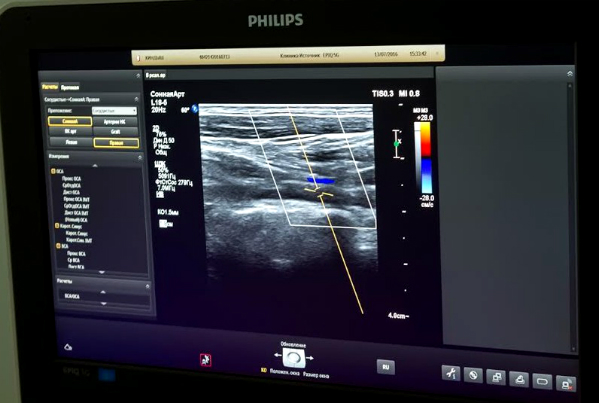

- эхокардиографию с цветным допплеровским картрированием (УЗИ сердца) – для оценки состояния полостей и клапанов сердца на новейшем аппарате экспертного класса производства Нидерланды);

- УЗИ сосудов шеи с функциональными пробами (для оценки проходимости и исключения критических сужений артерий, питающих головной мозг);

- эхокардиографию с цветным допплеровским картрированием (для оценки состояния полостей и клапанов сердца на новейшем аппарате экспертного класса производства Нидерландов);